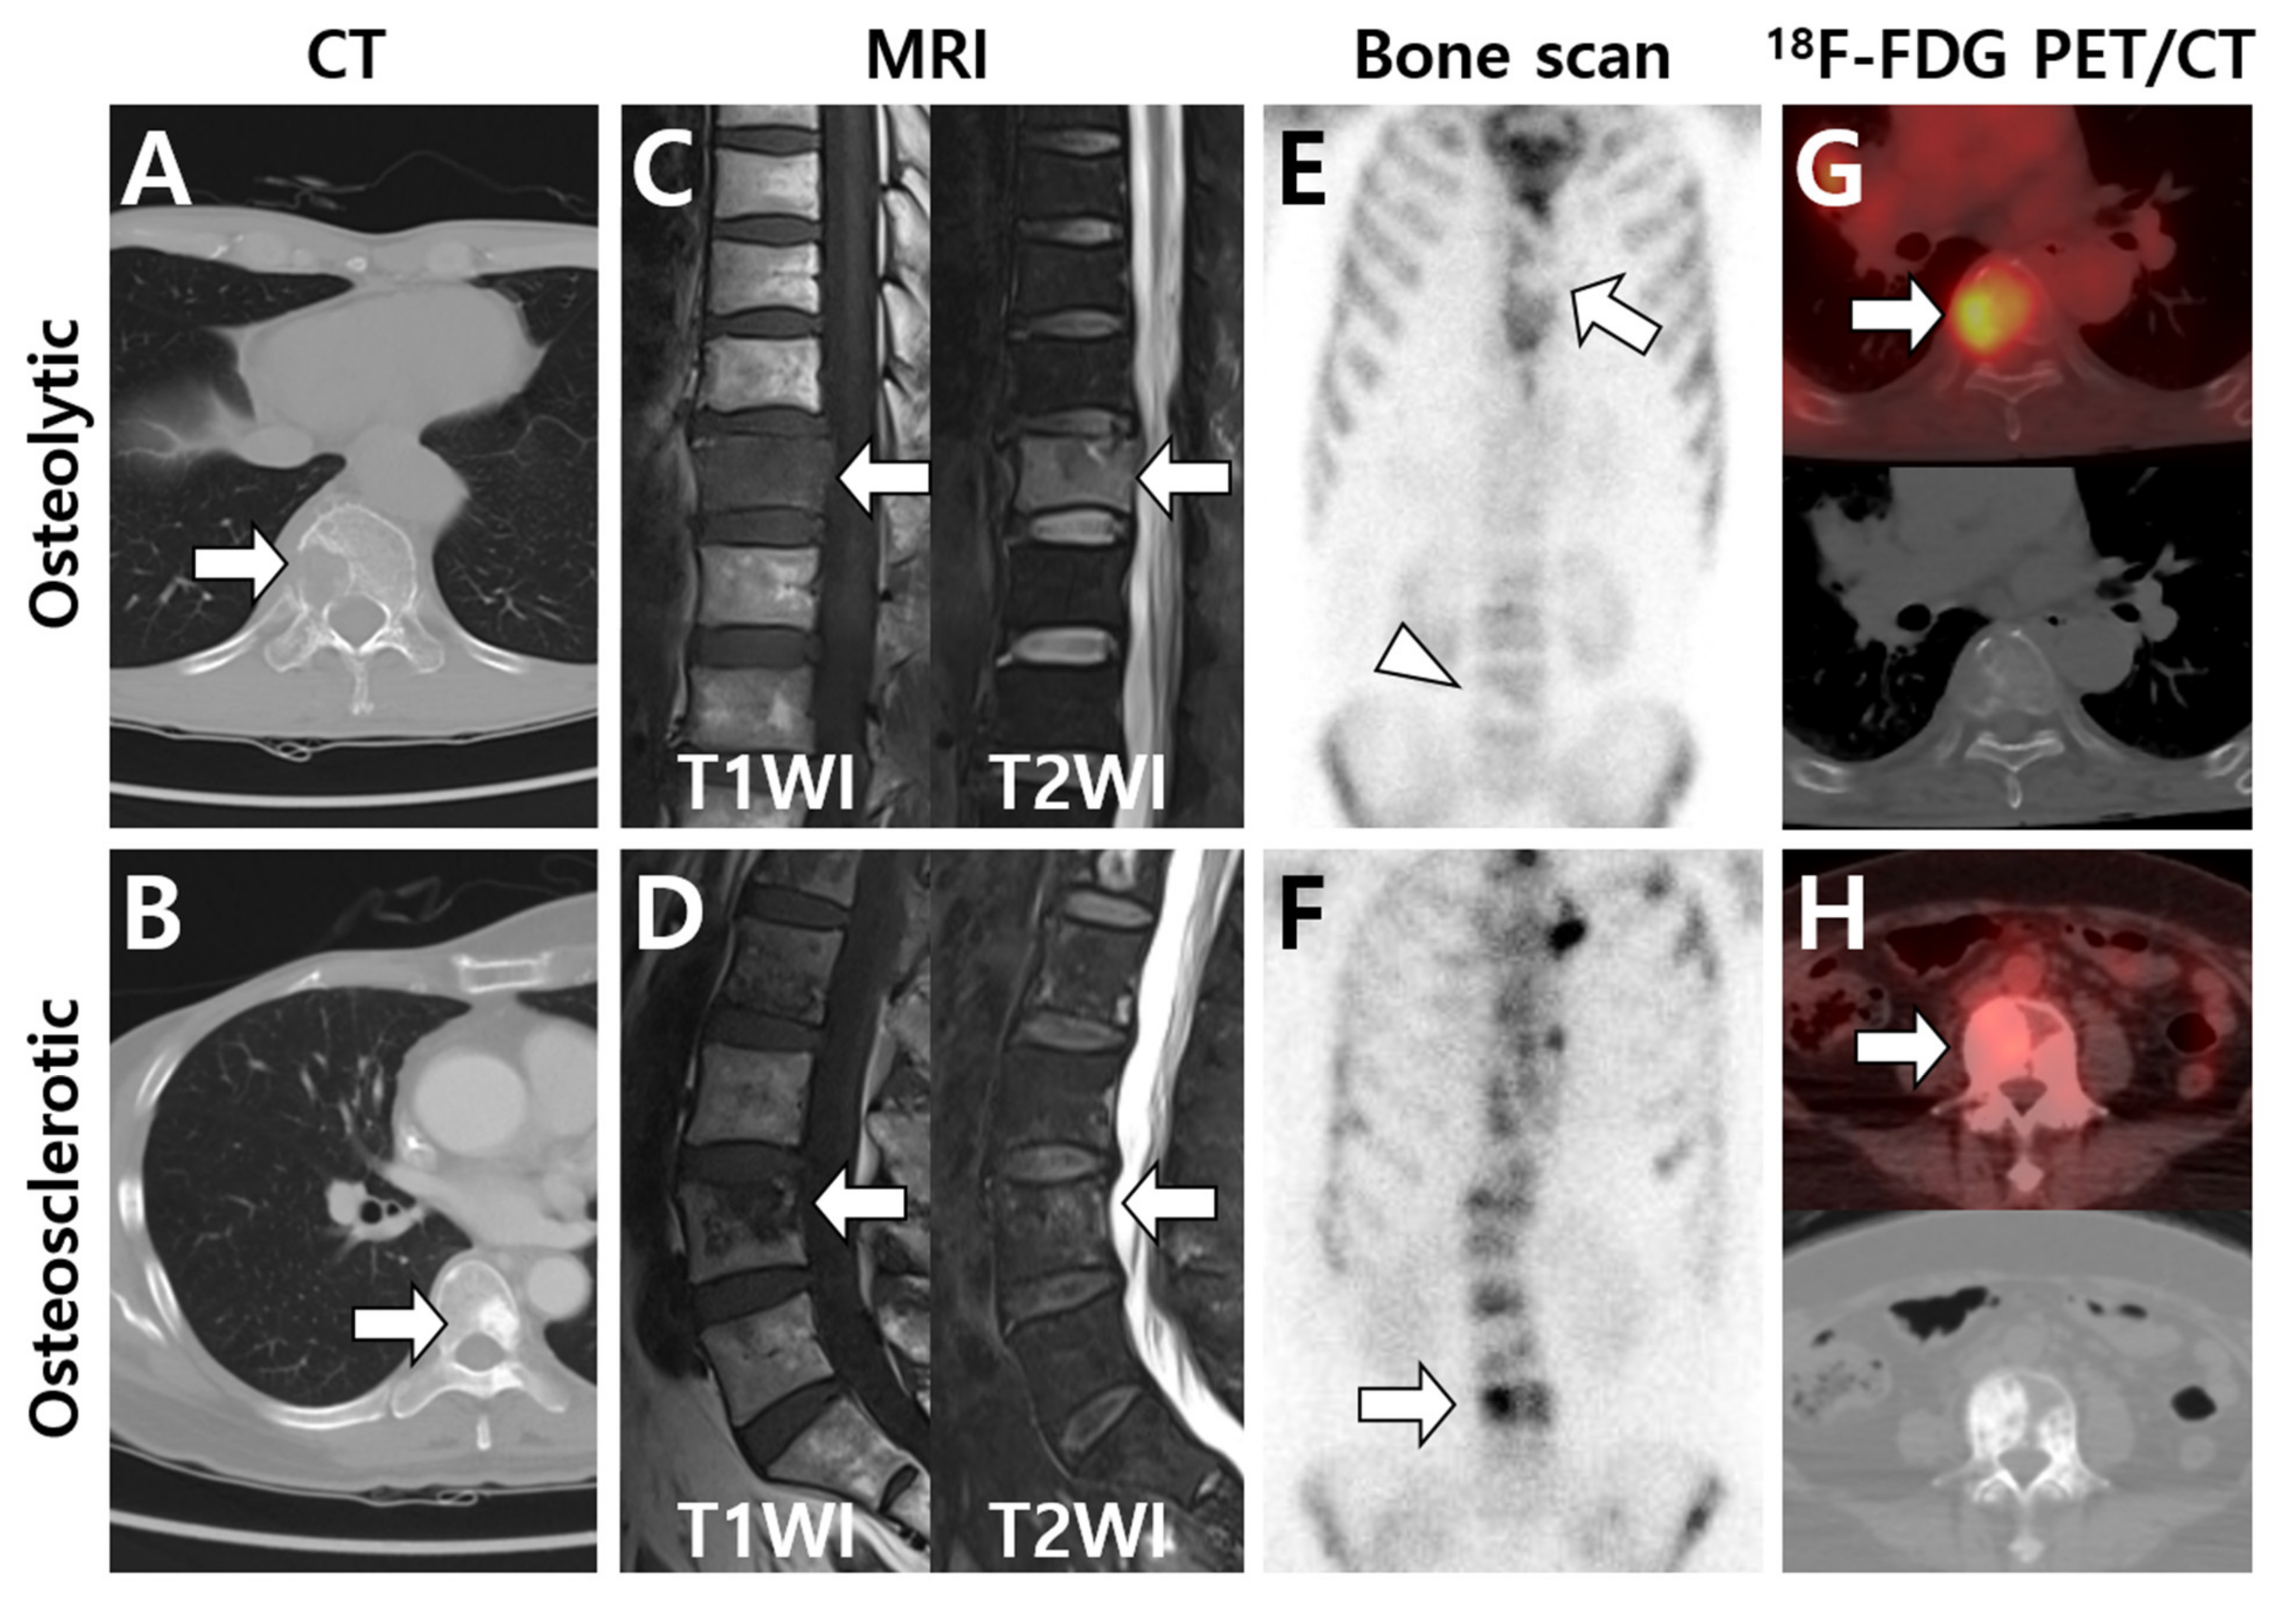

3.1. Multimodal Imaging According to the Primary Tumor Site and Histologic Type